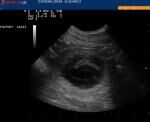

Klik op de afbeelding om de link te volgen Vandaag zijn we met Aymee naar Sleeuwijk geweest voor de echo en ze is drachtig!!!! Half juni verwachten we de pupjes.